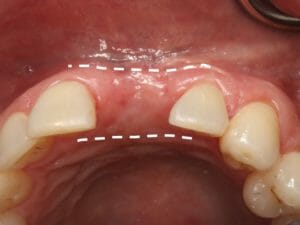

Ridge Preservation

Once a tooth is removed the bone shrinks to help the body efficiently use its resources. It is important to preserve the bone ridge before this happens. The most effective time for this is during a tooth extraction. During this procedure, the body normally forms a blood clot in a large empty space. After the wound contracts during healing, the bony ridge has become much smaller, possibly too small for an implant. When we perform grafting, wound contraction is prevented, leaving the bone ridge in its original shape and ready for an implant. If you'd like to learn more about bone grafting for dental implants, Jacksonville & surrounding areas contact us today at one of our four convenient locations.